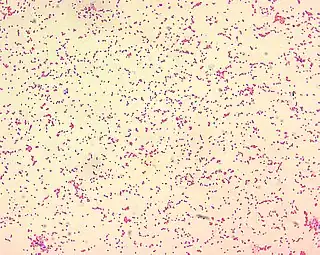

Células de Brucella spp. | ||